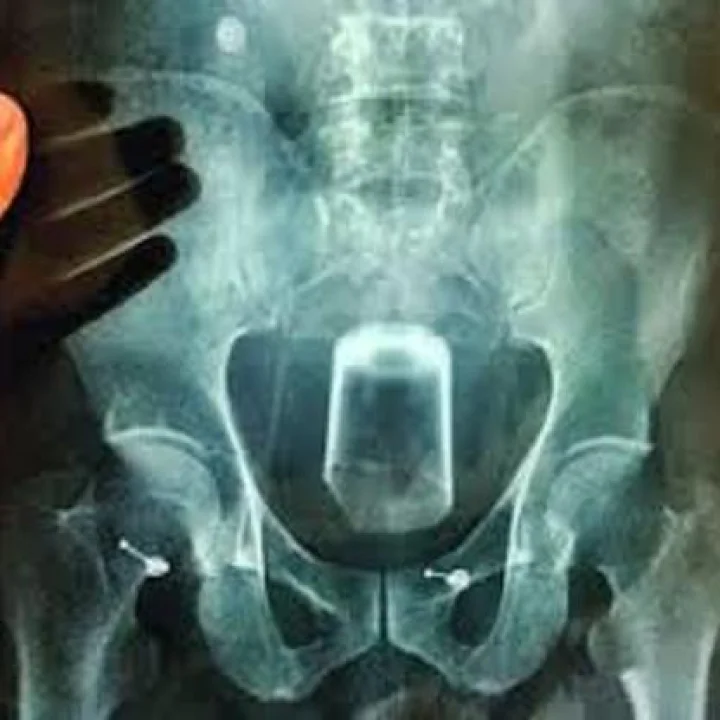

ಸಂತಾನಹರಣ ಶಸ್ತ್ರಚಿಕಿತ್ಸೆ ವೇಳೆ‌ ಮಹಿಳೆ ಸಾವನ್ನಪ್ಪಿದ್ದಾರೆ.

ಕಾರವಾರ ಜಿಲ್ಲಾ ಆಸ್ಪತ್ರೆಯಲ್ಲಿ ಸಂತಾನ ಹರಣ ಶಸ್ತ್ರಚಿಕಿತ್ಸೆ ವೇಳೆ ಮಹಿಳೆಯೊಬ್ಬರು ಸಾವನ್ನಪ್ಪಿರುವ ಬಗ್ಗೆ ಸೂಕ್ತ ತನಿಖೆ ನಡೆಸುವಂತೆ ಇಲಾಖೆಯ ಕಾರ್ಯದರ್ಶಿಗಳಿಗೆ ಆದೇಶ ನೀಡಿದ್ದೇನೆ ಎಂದು ವೈದ್ಯಕೀಯ ಶಿಕ್ಷಣ ಸಚಿವ ಡಾ.ಕೆ.ಸುಧಾಕರ್ ತಿಳಿಸಿದ್ದಾರೆ.

ಸಂತಾನಹರಣ ಶಸ್ತ್ರಚಿಕಿತ್ಸಾ ವೇಳೆ 30 ವರ್ಷದ ಮಹಿಳೆ ಸಾವನ್ನಪ್ಪಿದ್ದು ಅತ್ಯಂತ ದುರಾದೃಷ್ಟಕರ. ಇದು ಸರ್ವೇ ಸಾಮಾನ್ಯ ಶಸ್ತ್ರಚಿಕಿತ್ಸೆ. ಈ ವೇಳೆ ಸಾವು‌ ಸಂಭವಿಸಿರುವುದು ಜನರ ಆಕ್ರೋಶಕ್ಕೆ ಕಾರಣವಾಗಿದೆ.

ಯಾವ ಕಾರಣಕ್ಕೆ ಸಾವು ಸಂಭವಿಸಿದೆ‌ ಎಂಬುದು ತನಿಖೆಯಿಂದಷ್ಟೇ ಹೊರಬರಬೇಕು. ಈಗಾಗಲೇ ಇಲಾಖೆ ಕಾರ್ಯದರ್ಶಿಗೆ ತನಿಖೆ ನಡೆಸುವಂತೆ ನಿರ್ದೇಶನ ನೀಡಿದ್ದೇನೆ. ಒಂದು ವೇಳೆ ಶಸ್ತ್ರಚಿಕಿತ್ಸೆಯಲ್ಲಿ ಲೋಪವಾಗಿ ವೈದ್ಯರ ನಿರ್ಲಕ್ಷ್ಯ ಕಂಡು ಬಂದರೆ ಅವರ ವಿರುದ್ಧ ನಿರ್ದಾಕ್ಷಿಣ್ಯ ಕ್ರಮ ತೆಗೆದುಕೊಳ್ಳಲಾಗುವುದು ಎಂದರು.